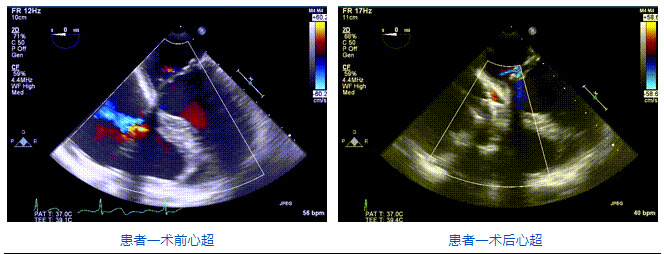

2021年12月24日,復(fù)旦大學(xué)附屬中山醫(yī)院葛均波院士團(tuán)隊成功應(yīng)用LuX-Valve Plus為一例極重度三尖瓣反流(TR)合并房顫、房缺的患者完成了經(jīng)血管三尖瓣置換術(shù),這是在前基礎(chǔ)上,本周完成的第三例經(jīng)血管三尖瓣置換手術(shù),葛均波院士、周達(dá)新教授等與心外科魏來教授、賴顥教授,心超室的潘翠珍教授、李偉教授及麻醉科的郭克芳教授共同完成了本周手術(shù),均獲得圓滿成功!患者術(shù)后超聲顯示無TR,臨床癥狀明顯改善。本周手術(shù)的成功也為LuX-Valve Plus救治性臨床研究添上了濃墨重彩的一筆。

三例患者入院后,葛均波院士團(tuán)隊周達(dá)新教授、潘文志教授、張源博士、陳莎莎博士及心超室的潘翠珍教授、李偉教授對患者的情況進(jìn)行詳細(xì)評估和討論,最終決定為三例患者選擇LuX-Valve Plus40mm、50mm和50mm型號的瓣膜進(jìn)行手術(shù)治療。手術(shù)后即刻拔除氣管插管,術(shù)后患者三尖瓣反流癥狀得到顯著改善,復(fù)查心超結(jié)果顯示人工三尖瓣瓣膜支架固定穩(wěn)定,瓣葉關(guān)閉形態(tài)未見異常,未見明顯反流。